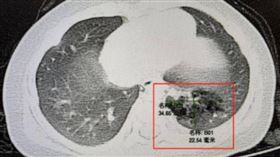

台科大以AI辨CT掃描影像 2秒辨識多類病灶

台科大教授王靖維團隊開發「通用3D病灶分割AI模型」...

2024/07/22 12:08